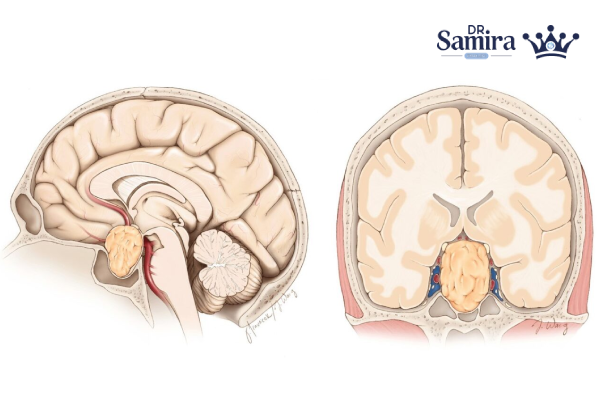

پینئوبلاستوم یکی از تومورهای نادر و بدخیم مغز است که در غدهای کوچک به نام غده پینهآل (Pineal gland) در مرکز مغز شکل میگیرد. این غده وظیفه ترشح هورمون ملاتونین را دارد که چرخه خواب و بیداری بدن را تنظیم میکند. تومور پینئوبلاستوم بیشتر در کودکان و نوجوانان دیده میشود و از آنجا که سرعت رشد بالایی دارد، در صورت تأخیر در تشخیص میتواند به سایر بخشهای مغز و حتی نخاع گسترش یابد. تشخیص زودهنگام و درمان سریع، نقش حیاتی در کنترل این بیماری دارد.

پینئوبلاستوم نوعی تومور بدخیم سیستم عصبی مرکزی است که از سلولهای نابالغ عصبی در ناحیه غده پینهآل منشأ میگیرد. این سلولها بهجای توقف رشد در زمان مناسب، به تکثیر غیرقابل کنترل ادامه میدهند و تودهای سرطانی را شکل میدهند. به دلیل قرار گرفتن غده پینهآل در عمق مغز، این تومور زمانی شناسایی میشود که اندازه آن افزایش یافته و باعث بروز علائم فشاری در مغز شده است. پینئوبلاستوم جزو تومورهای درجه چهار محسوب میشود و از تومورهای خوشخیم همان ناحیه مثل پینئوسیتوما خطرناکتر است.

پینئوبلاستوم از نظر شدت، در بالاترین درجه بدخیمی یعنی درجه چهار (Grade IV) قرار دارد. این یعنی تومور رشد سریع و تمایل زیادی به گسترش دارد. در مرحله اولیه، تومور فقط به غده پینهآل محدود است، اما با پیشرفت بیماری ممکن است به بطنهای مغزی یا محور نخاعی انتشار پیدا کند. به همین دلیل، مرحلهبندی بر اساس محل گسترش تومور و وجود سلولهای سرطانی در مایع مغزی انجام میشود. شناسایی دقیق مرحله بیماری نقش مهمی در تعیین نوع درمان دارد، زیرا درمان در مراحل اولیه میتواند نتایج بسیار بهتری به همراه داشته باشد.